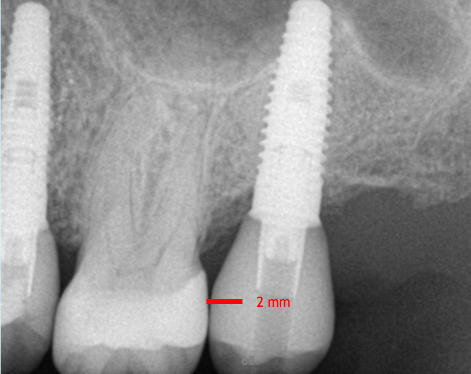

Fig 2. If the distance is less than 7 mm, an unsightly gray dot may result.

Figure 2

The author teaches "restorative address 73-422," a metaphorical street address, as the best method to help navigate an implant start to finish, where each number corresponds to a significant measurement. These measurements can be viewed by looking at the cross-section of a cone-beam computed tomography (CBCT) scan. The first number in the address, "7," represents the distance that the restorative platform should be from the desired occlusal table (Figure 1). An abutment 5 mm in length will minimize the chances of the restoration dislodging from the abutment. Then, above coronal to the abutment, there should be 2 mm of restorative material to ensure a strong restoration that will not fracture or break. Together, the abutment length of 5 mm plus the 2 mm of restorative material equals 7 mm. If the distance between the restorative platform of the implant abutment and the desired occlusal table is less than 7 mm, it will be difficult to mask out the screw-access hole and may result in an unsightly gray dot in the middle of the implant restoration (Figure 2). If the distance is slightly greater than 7 mm, that is acceptable, but it should not be less.